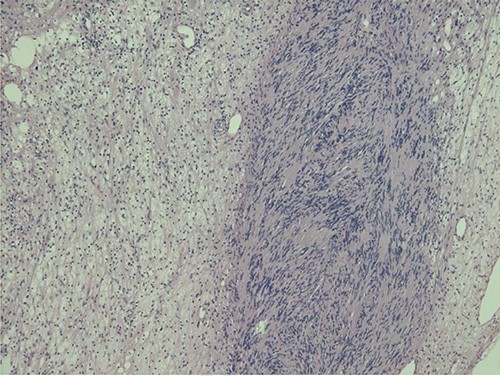

Histopathological examination revealed typical features of schwannoma (Figs 2 and 3). Tumour was well demarcated, encapsulated, composed of spindle cells, organized in a palisading fashion and had hypocellular myxoid component with large vessels. Tumour cells had an ill-defined cytoplasm and elongated nucleus. There was no mitotic activity.

Biphasic tumour: compact hypercellular Antoni A area (right) and myxoid hypocellular Antoni B area (left).

Macroscopically schwannoma looks like yellowish-white, well-circumscribed mass [1, 6]. Microscopically, the baseline features of schwannoma are Antoni type A tissue and Antoni type B tissue [1, 4]. Necrosis, haemorrhage and cystic degeneration are other specific features [1, 4].